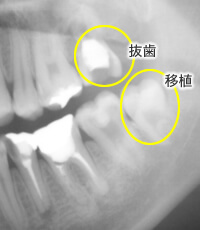

歯の移植・再植

根の先の病巣が大きいなど、状態が良くない歯の場合、根の治療のみでは治癒は期待できず、やむなく抜歯になってしまうケースがあります。 その場合、他の歯(例えば、親知らず)を抜いた部分に戻す移植法と、患歯を1度抜いて治療して戻す再植法があります。

■移植法